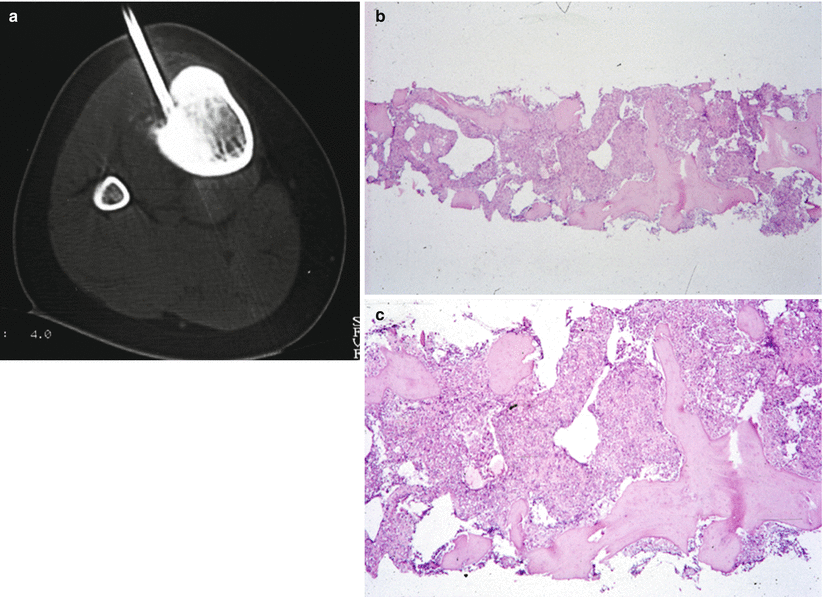

WebAbstract. Although primary bone tumors are relatively uncommon, appropriate imaging evaluation is essential when they are suspected or incidentally detected. In almost all cases, radiographs are the most appropriate initial imaging study for screening and characterization of primary bone tumors.